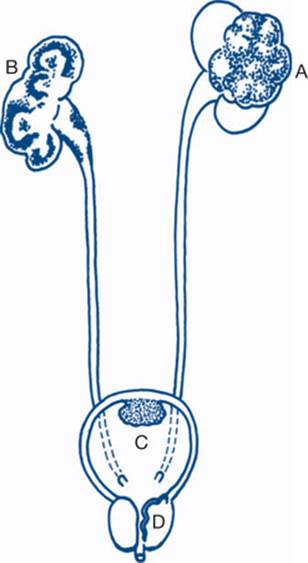

Figure 9.2a Cystoscopy and ureteric catheterisation

A: tip of cystoscope with elevating bridge; B: trigone of bladder; C: ureteric oriface; D: interureteric bar